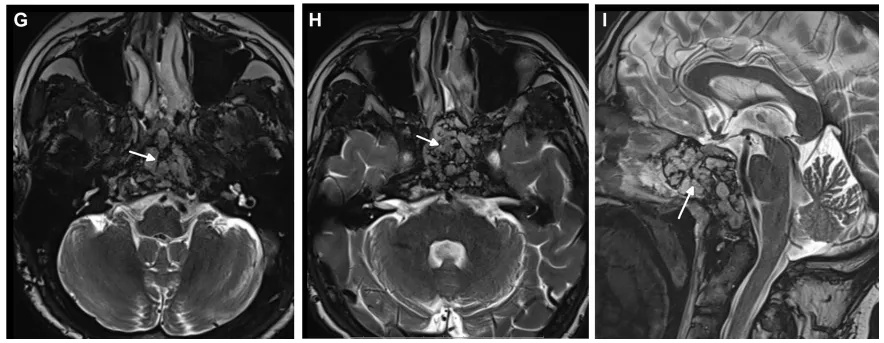

术后MRI证实肿瘤完全切除,无脑水肿和脑出血。术后2月随访,内镜检查没有发现结痂,患者也没有抱怨任何鼻腔不适。

▼术后MRI证实肿瘤完全切除,显示用于术后残腔重建填充的脂肪(白色箭头表示脂肪移植)。